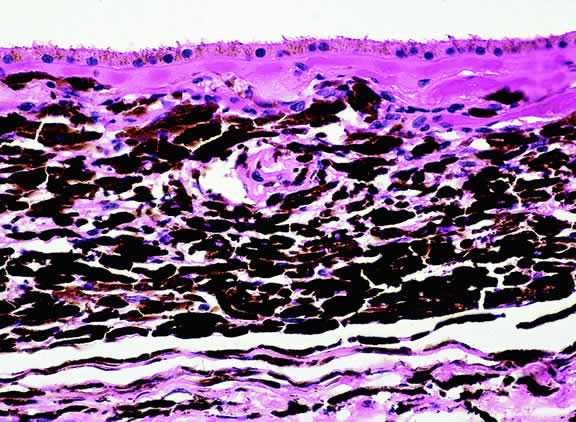

The substrate for the development of melanoma in white patients with ocular melanocytosis is a diffuse nevus that affects all, or part, of the uveal tract. Clinically, the nevus typically is evident as hyperchromic heterochromia iridum, patchy slate gray epibulbar pigmentation, and a darker aspect of the fundus compared with the fellow eye (Fig. 8). A sector of uvea is affected in some patients, however, and the nevus may spare the iris. The uvea in congenital melanocytosis is thickened by an increased number of heavily pigmented nevus cells similar to those found in melanocytomas (Fig. 9). RPE abnormalities such as drusen often develop on the surface of the thickened choroid.48 The sclera also contains patchy foci of pigmentation. The slate gray conjunctival pigment reflects the presence of dendritic melanocytes on the epibulbar tissues deep to the conjunctiva. Nevus of Ota does not predispose to conjunctiva melanoma. However, patients rarely may develop melanomas of the orbit49–51 and even leptomeninges.1,52,53 White patients who have congenital ocular or oculodermal melanocytosis should be followed periodically because of the increased risk of uveal melanoma.54

Fig. 9. Congenital ocular melanocytosis, choroid. Choroidal stroma is thickened by infiltrate of heavily pigmented benign melanocytes. Patient had iris heterochromia and skin pigmentation consistent with nevus of Ota. (Hematoxylin-eosin, × 100.)